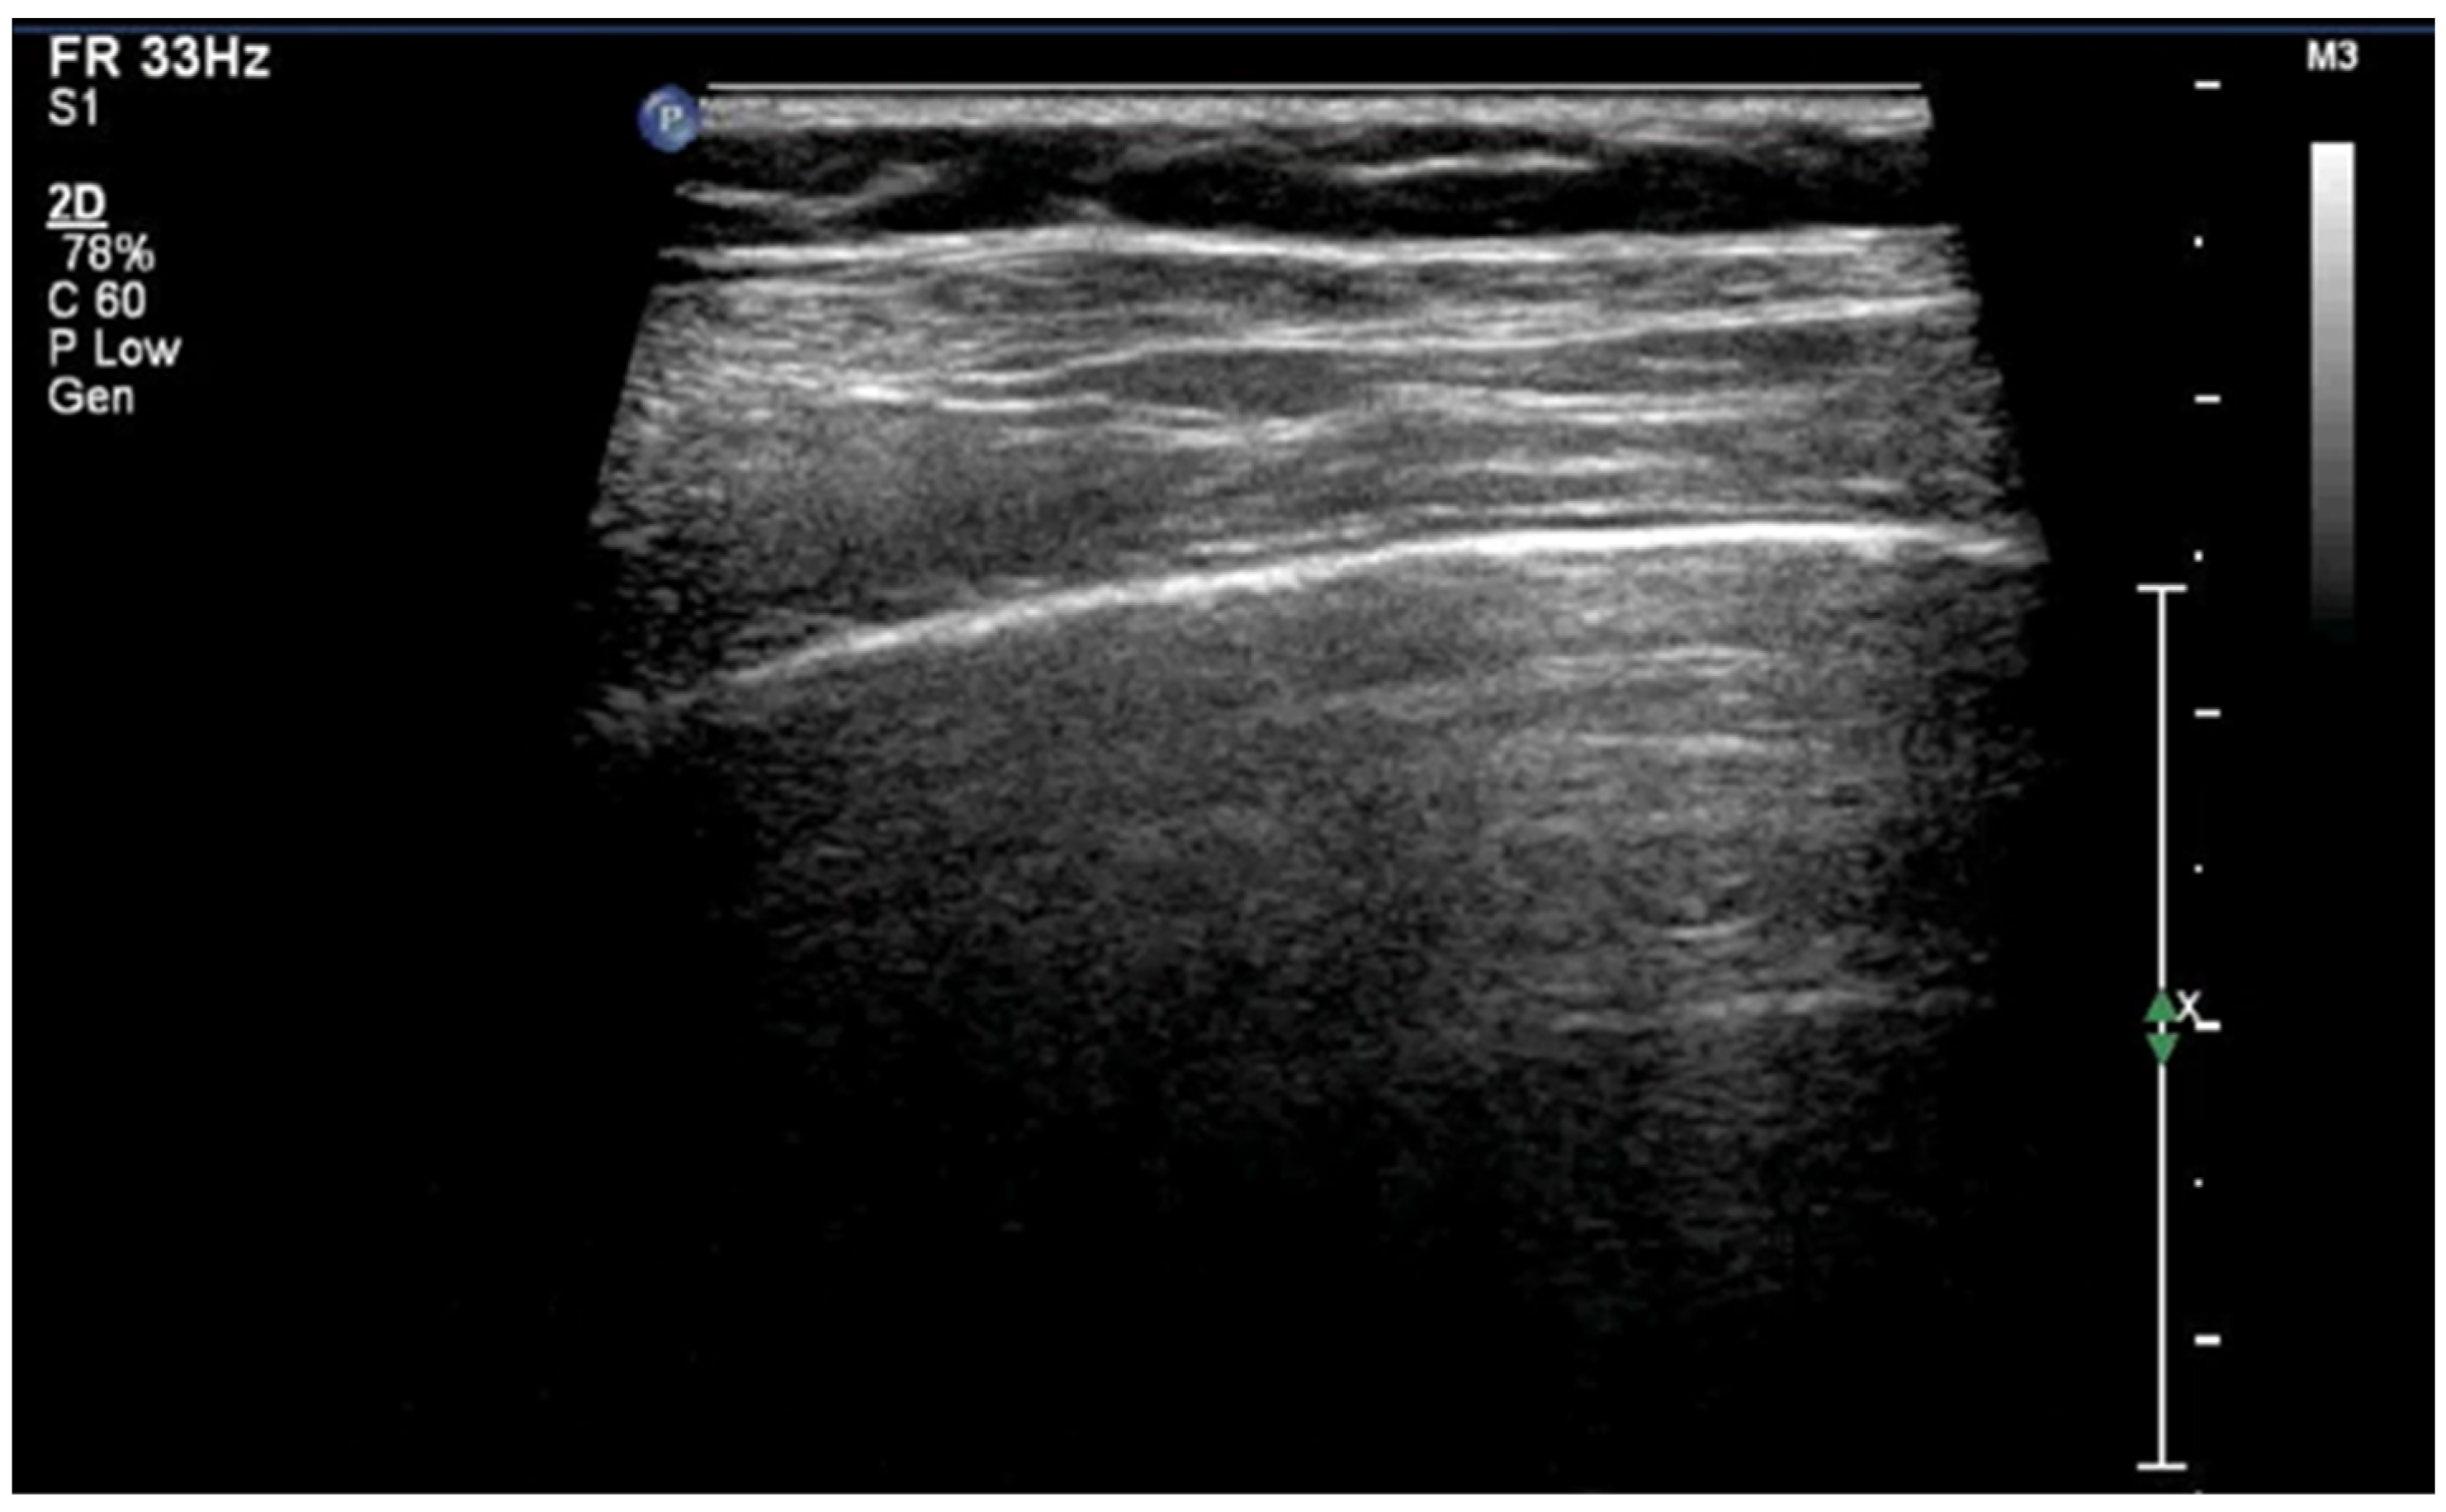

3.1.5. Sea-Shore Sign

The “sea-shore sign” is a characteristic ultrasound finding observed during M-mode (motion mode) scanning, and is indicative of normal lung sliding. In this pattern, the pleural line and overlying chest wall structures produce a series of horizontal echogenic lines, representing static tissues (Figure 6).

Upper image: LUS with normal A-Lines in B (bright)-mode. The simultaneous M (motion)-mode image (lower image) reveals series of horizontal echogenic lines which represent the pleural line and its reverberations (A-lines), as well as the air-filled alveoli with a granular/sandy appearance (more prominent in real time scan). These in combination produce the seashore sign.

In contrast, the underlying lung parenchyma, which moves in synch with respiration, generates a granular or sandy appearance due to the dynamic motion of air-filled alveoli [17]. This combination creates the visual effect of waves (static layers) above and sand (with a dynamic speckled texture) below, thus producing the so-called “sea-shore sign”. The presence of this sign confirms normal apposition and movement of the visceral and parietal pleurae, and can be used to effectively rule out pneumothorax at the examination site. The “sea-shore sign” is considered to be a reliable and non-invasive indicator of intact lung sliding, and is frequently used in both adult and neonatal lung ultrasound to assess respiratory function and pleural integrity [5,6,15,22,23].

When this sign is absent, uniform horizontal straight lines, known as the stratosphere sign or “barcode sign”, appear, indicating pneumothorax as a possible cause [18,24].